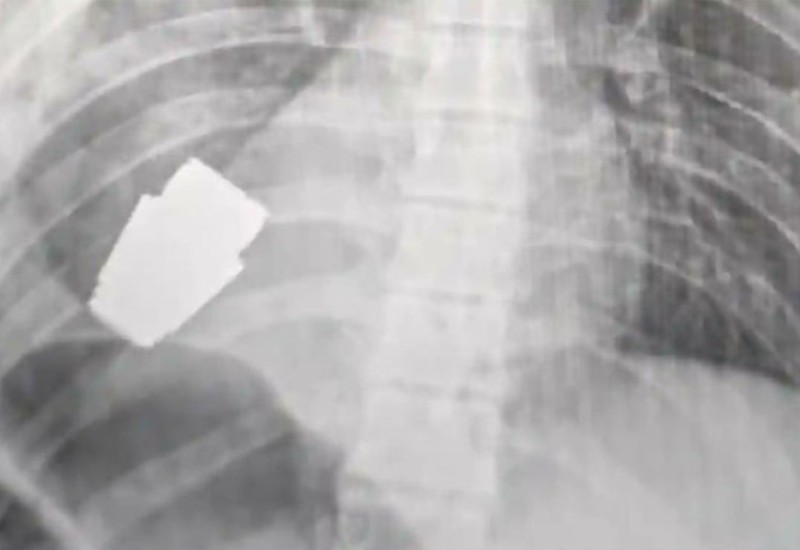

Hana Malijar, zamjenica ukrajinskog ministra odbrane, podijelila je fotografije rendgenskog snimka na kom se jasno vidi granata u tijelu vojnika.

„Vojni doktori su uspješno sproveli operaciju uklanjanja granate iz grudi vojnika“, navela je Malijarova.

Savjetnik ukrajinskog ministra unutrašnjih poslova, Anton Geraščenko, rekao je da su dva stručnjaka uspješno demontirala municiju, ističući da će obavljena procedura ući u medicinske udžbenike.

Operacija je obavljena bez korišćenja elektrokoagulacije, uobičajenog metoda za kontrolisanje krvarenja tokom zahvata, zbog straha da bi moglo da aktivira granatu.